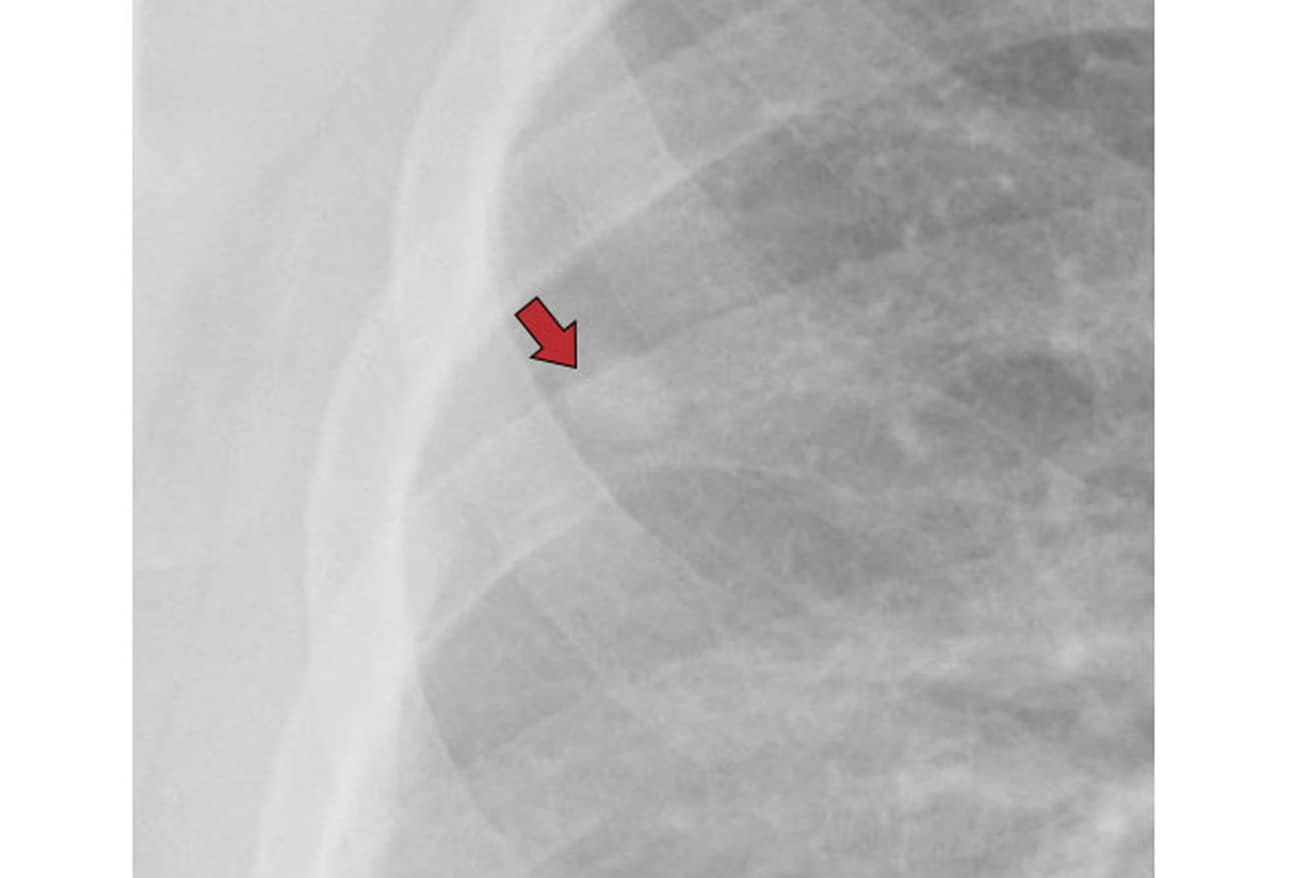

Pulmonary Coccidioidomycosis Pictorial Review of Chest Radiographic Chest X Ray Findings Valley Fever coccidioidomycosis, a fungal infection that can be categorized as acute, disseminated, or chronic, is discussed in. approximately sixty percent of patient are entirely asymptomatic making identification of infected individuals. valley fever is an infection that occurs when the spores of the fungus coccidioides immitis enter your body through the lungs. symptoms of primary coccidioidomycosis, in decreasing. Chest X Ray Findings Valley Fever.

Figure 2. Chest Xrays Findings Acute Respiratory Failure Secondary Chest X Ray Findings Valley Fever the chest radiograph may suggest coccidioidomycosis, but confirmation with another diagnostic test is mandatory. coccidioidomycosis, a fungal infection that can be categorized as acute, disseminated, or chronic, is discussed in. symptoms of primary coccidioidomycosis, in decreasing order of frequency, include fever, cough, chest pain, chills, sputum production, sore. valley fever is an infection that occurs when. Chest X Ray Findings Valley Fever.